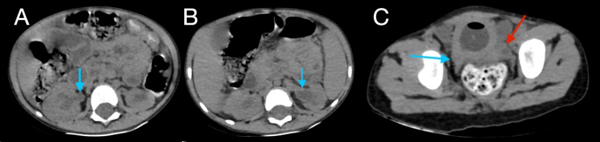

En la tomografía se evidenció presencia de S1-S2 con ausencia del resto de cuerpos sacro-coxígeos, así como hipodensidad a nivel de la médula que podría sugerir siringomielia (Figura 1). También se encontró falta de unión de algunos elementos posteriores a nivel de L5-S1 (Figura 2), lo que sugiere el diagnóstico de síndrome de regresión caudal asociado a probable siringomielia y probable vejiga neurogénica dado engrosamiento marcado de las paredes vesicales (Figura 3). Además, se encontró dilatación ureteropielocalicial de forma bilateral (Figura 4). A raíz de estos hallazgos, se solicitó una valoración por genética clínica, la cual determinó que la paciente cumple con los criterios clínicos de regresión caudal y tiene antecedentes de diabetes gestacional insulino-dependiente, lo cual es un factor de riesgo.

Figura 3. Tomografía de abdomen, cortes axiales, donde se muestra dilatación de la pelvis renal derecha (A), e izquierda (B), así como de los trayectos ureterales hasta distal y discreto engrosamiento de sus paredes (C, flecha azul derecho, flecha roja izquierdo).

En este caso, se encontró una ausencia parcial sacro coxígea con preservación de S1 (Figura 1), asociada a no unión de elementos posteriores de L5 y S1 (Figura 2), siendo un síndrome de regresión caudal tipo I según Pang, asociado a alteraciones genitourinarias dadas por hidronefrosis bilateral (Figura 3) y engrosamiento de las paredes vesicales (Figura 4).